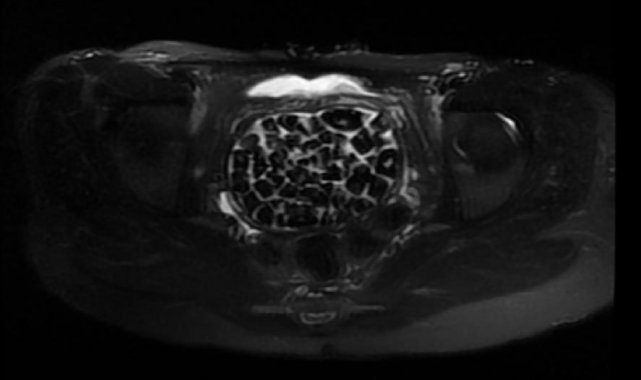

Hastasının durumuna yönelik konuşan Üroloji Uzmanı Doç. Dr. Erkan Erkan, "Hastamızın 2004 yılında doğduğunu ardından doğar doğmaz ekstrofi vezika dediğimiz 50 binde bir görülen bir anomaliden dolayı art arda ameliyatlar geçirdiğini öğrendik. 10 yaşında yine bir ameliyat geçirmişti, gerekli görüntüleme ve tetkiklerimizi yaptırdık. Normalde mesanesinin olması gereken yerin hemen arka kısmında taşlarla dolu bir kese olduğunu gördük, bunun üzerine ek görüntülemeler; MR çektirdik. Hastamız çelişkili açıklamalar almıştı, kendi radyolojik kliniğimiz ve edindiğimiz konsültasyonlarda taşların mesanede değil vajinal boşlukta oluştuğunu düşündük, bir planlama yaptık. Kadın doğum hocamızın da çabasıyla taşları tamamen temizledik ardından ileride normal bir hayat sürmesi bakımından oraya plastik cerrahi yaptık. 287 adet taş çıkardık, pratikte gerçekten görünce çok şaşırdık çünkü bu aynı zamanda literatürde çok nadir görülen bir olay. Biz ameliyata hazırlanırken de teorik olarak biraz araştırdık. Literatürde gördüğümüz kadarıyla buna benzer bu tanıma uyan bir vaka vardı. Literatürde sanırım yayınlanmış 2'nci vaka olacak. Farkındalık çok önemli, bilinçli bir hastamız vardı. Doğumsal anomaliyle doğan çocuklarımızda ileride bunlara bağlı bazı sıkıntılar çıkabileceğinin öngörülmesi lazım. İlgili tedavilerini alsalar bile düzenli takiplere gelmeleri gerekiyor. İleride eğer dikkat etmezse ki zannetmiyorum, tekrarlayabilir. Bu rahatsızlık ekstrofi vezikal epispadias durumu çok nadir bir durum" dedi.

Genç kızın uzun süredir devam eden karın ağrısı olduğunu söyleyerek sözlerine başlayan Jinekolojik Onkoloji Uzmanı Op. Dr. Emin Erhan Dönmez, "Mesane taşları olduğu düşünülerek daha büyük bir hastaneye refere edilmiş. Aramızda mini bir konsey yaparak muayene ettik. Vajen bir hazne görevi görerek orada durağan bir idrar, uzun süre beklediği için idrar içindeki minerallerde çökerek taşlar oluşmuş. Mesanedeki idrarın vajene akmış olabileceği ve vajende göllenen idrar nedeniyle taşların burada oluşacağını düşündük, ameliyatımızı planladık. Ameliyata tanı amaçlı girmiştik, sistoskopi (Mesane gibi idrar yollarını kapsayan kısımlardaki rahatsızlıkların teşhis ve tedavisinde kullanılan endoskopik bir yöntem) dediğimiz ameliyatı Erkan Hocam ile birlikte gerçekleştirdik. Önce mesaneyi bir görüntüledik, mesane tabanına yaklaşık 2-3 cm'lik bir alandan vajene fistülize olduğunu gördük. Mesaneden vajene geçtiğimiz esnada tüm vajenin taşlarla dolu olduğunu gördük. Tanı amacıyla girdiğimiz ameliyatta her şey de olağan gittiği için tedaviye geçtik. Taşların çıkabileceği kadar bir genişlik sağladık. Daha sonra yaklaşık en büyüğü 2,5 cm boyutlarında olan, irili ufaklı 287 tane taşı ameliyat esnasında çıkarmış olduk. Taşların tekrarlamaması için idrarın göllenmemesi, en azından dışarıya rahatça boşalabilmesi için vajinal rekonstrüksiyonu sağladık. Ameliyatta da herhangi bir problem yaşamadık. Literatürü Erkan Hocam ile birlikte değerlendirmiştik. Primer olarak vajende birikmiş olan bu kadar çok sayıda taşla ilgili bir makale görmedik, rastlamadık" dedi.